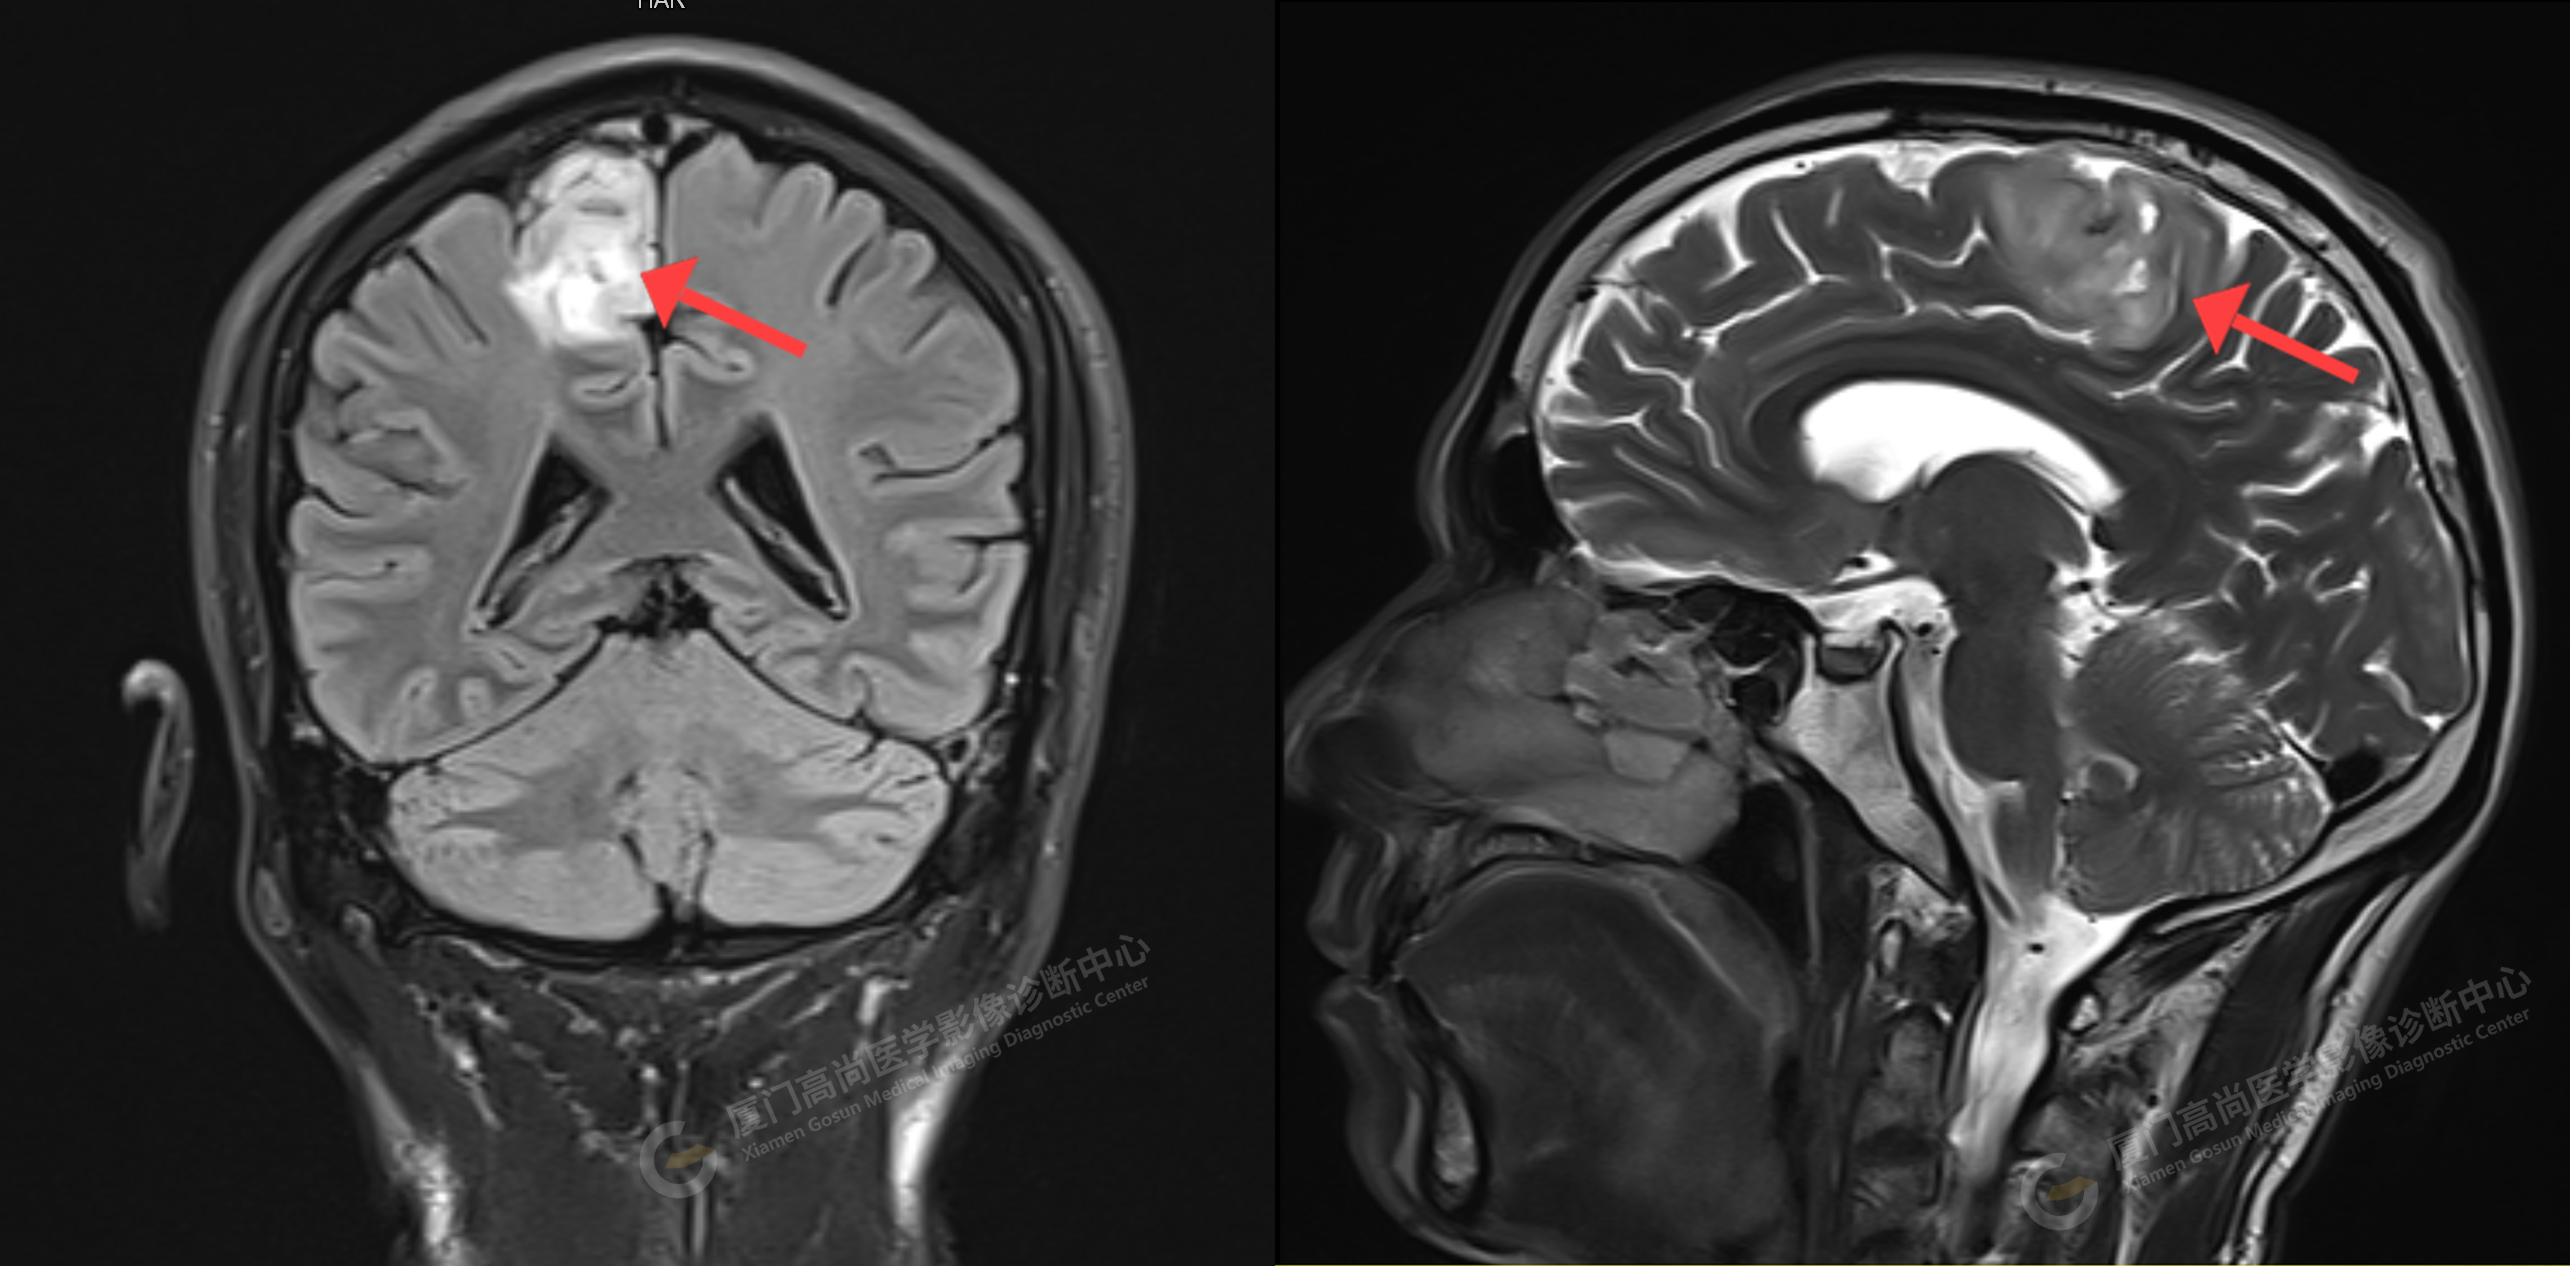

中心病例2:許先生在我中心進(jìn)行顱腦磁共振平掃發(fā)現(xiàn)右側(cè)額部見(jiàn)一枚占位性病變,雙側(cè)大腦白質(zhì)少量斑點(diǎn)癥。考慮為膠質(zhì)細(xì)胞瘤(少突膠質(zhì)細(xì)胞瘤?)(影像圖片見(jiàn)上)